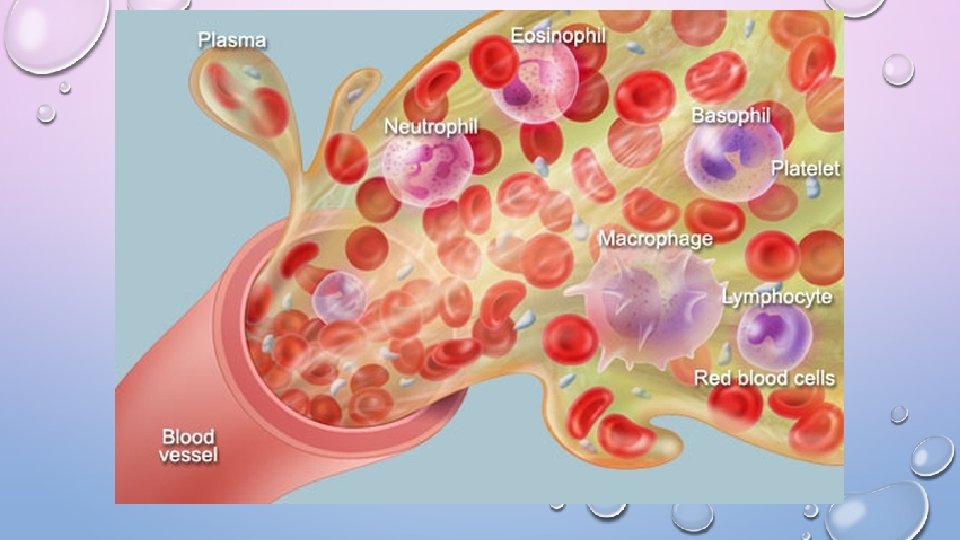

INTRO. TO CIRCULATORY SYSTEM • HUMANS HAVE A CLOSED CIRCULATORY SYSTEM • BLOOD IS CONFINED TO VESSELS • 5 LITERS IN 1 HUMAN = 7 -8% OF YOUR WEIGHT • 3 DROPS OF BLOOD IS 1 BILLION RBC • 600 RBC = 40 PLATELETS AND 1 WBC

BLOOD COMPONENTS 1. PLASMA- LIQUID CONTAINS: • CLOTTING FACTORS • HORMONES • ANTIBODIES • GASES, WASTE, NUTRIENTS

BLOOD COMPONENTS 2. ERYTHROCYTES- AKA RED BLOOD CELL • CARRY HEMOGLOBIN, • NO NUCLEUS, 120 DAY LIFE, • CANNOT REPAIR THEMSELVES, ERYTHROPOIESIS

3. LEUKOCYTES- WHITE BLOOD CELLS FORMED IN BONE MARROW, FIGHT INFECTION 5 TYPES • NEUTROPHIL - 58%; MAIN DEFENSE, PHAGOCYTOSIS • LYMPHOCYTE- 30%; B AND T CELLS, IMMUNITY, RECOGNITION • EOSINOPHIL- 2%; PARASITE/ALLERGIES • GRANULOCYTE- DIGESTIVE ENZYME

3. LEUKOCYTES- WBC 5 TYPES (CONTINUED) • BASOPHIL- 1%, ALLERGIES? ? ? UNKNOWN • GRANULOCYTE • MONOCYTE- 4% CREEPERS • GO AND LIVE IN TISSUES AND COME OUT WHEN NEEDED • GRANULOCYTE

CLOT IT UP! • 4. THROMBOCYTES- PLATELETS • CLOT BLOOD BY STICKING TOGETHER AND SECRETING PROTEIN CALLED FIBRIN • SUPER SMALL